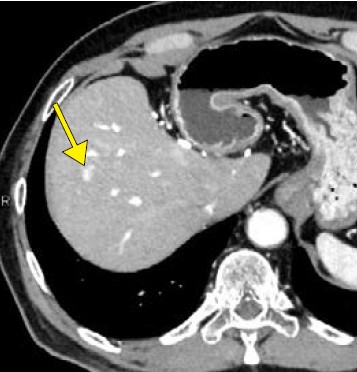

Aquilion ONE / INSIGHT Editionは、ハードウエア系の一新で0.24秒のガントリ回転速度など基本性能を向上させ、AI技術によって開発された超解像画像再構成技術「Precise IQ Engine(PIQE)」、モーションアーチファクト低減技術「CLEAR Motion」などを搭載したフラッグシップCTである。画像の評価を佐藤部長は、「PIQEによる再構成は予想以上にノイズが低減されており、従来と同等の線量でも大きく画質が向上しています。血管系の精度向上はもちろんですが、肝実質や膵実質など実質臓器についてもノイズの低減で読影がしやすくなっています。読影では消化管も見ていますが、解像度の向上とPIQEによってクリアに描出されて、管腔構造の連続性が認識しやすく、壁構造のコントラストが向上して粘膜変化をとらえやすくなっており評価が容易になっていると感じます」と述べる。PIQEは肺野を除く全例で適用されている。肝細胞がんの症例(図1)では、3か月前にIVR-CTの80列で撮影した画像に比べて、ほぼ同条件で撮ったAquilion ONE / INSIGHT Editionの画像では早期濃染を示す小病変がより明瞭に描出されている。また、胃潰瘍の症例では、通常の造影検査で粘膜の欠損や粘膜下の浮腫が明瞭に描出されていた。佐藤部長は、「従来は小さい消化管病変は疑いを指摘するにとどまっていましたが、より確信を持って診断できます」と述べる。

図1 肝細胞がん a

図1 肝細胞がん b

a:Aquilion PRIME(AIDR 3D

b:Aquilion ONE / INSIGHT Edition(PIQE)